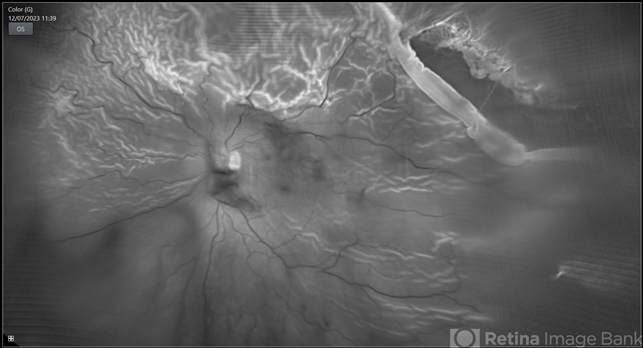

- rrd, chronic retinal detachment, peripheral lattice degeneration

- 78-year-old man with history of defective following cataract surgery showed total retinal detachment on examination